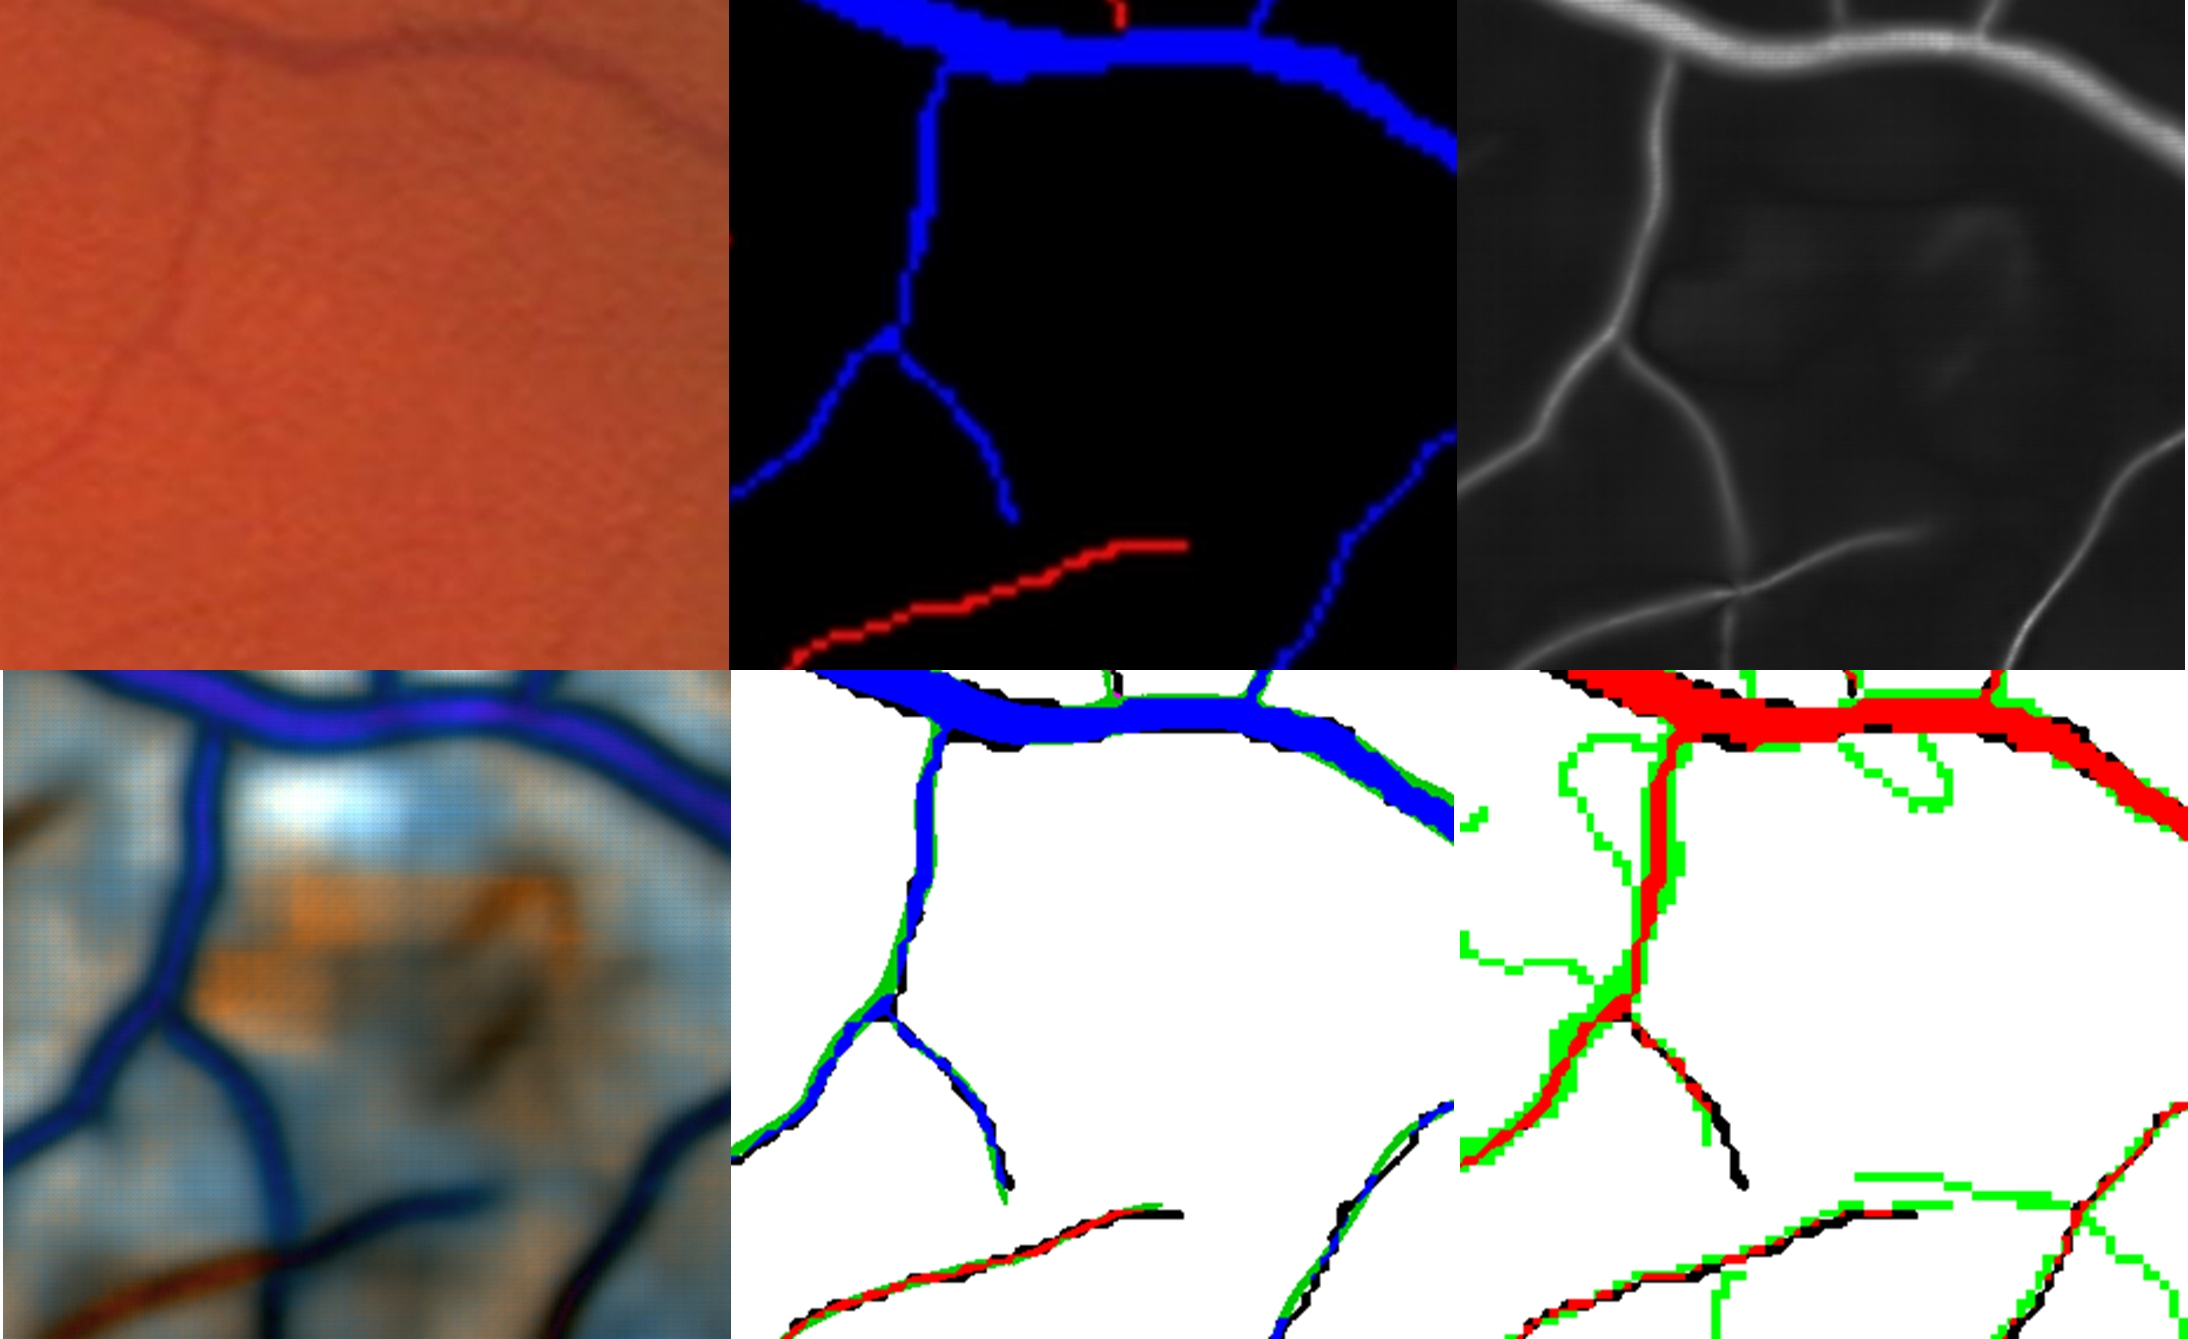

Analysis of the false negatives and false positives in the fundus images can help to better understanding the remaining errors. In Fig. 11 and Fig. 12, two examples of outputs are given. The false negatives are mainly small vessels that are not detected at all or are offset from their ground-truth locations. In Fig. 12, some hemorrhages are also detected as vessels. In the vessels wider than 4 pixels, the false positives are concentrated at the borders of those vessels. In the vessels narrower than 4 pixels, the false positives are mainly due to their being offset from their ground-truth locations. Misclassification of arteries as veins or vice-versa is mainly concentrated on vessels narrower than 4 pixels. There are also some arteries and veins interlaced or very close to each other, also causing misclassification.

Refer to caption

Figure 11: Classification results with CNN 6D BP + LSP on 4th test image from DRIVE (Acc. = 95.4%). Top row from left to right: 1) original image, 2) ground truth, 3) Vessel probability map. Bottom row from left to right: 1) CNN output probability map (blue: veins; red: arteries; gray: background), 2) hard classification, 3) error map (blue: true veins; red: true arteries; black: false negatives; green: false positives; white: true background).

Figure 12: Classification results with CNN 6D BP + LSP on 14th test image from DRIVE (Acc. = 95.3%). Top row from left to right: 1) original image, 2) ground truth, 3) Vessel probability map. Bottom row from left to right: 1) CNN output probability map (blue: veins; red: arteries; gray: background), 2) hard classification, 3) error map (blue: true veins; red: true arteries; black: false negatives; green: false positives; white: true background).